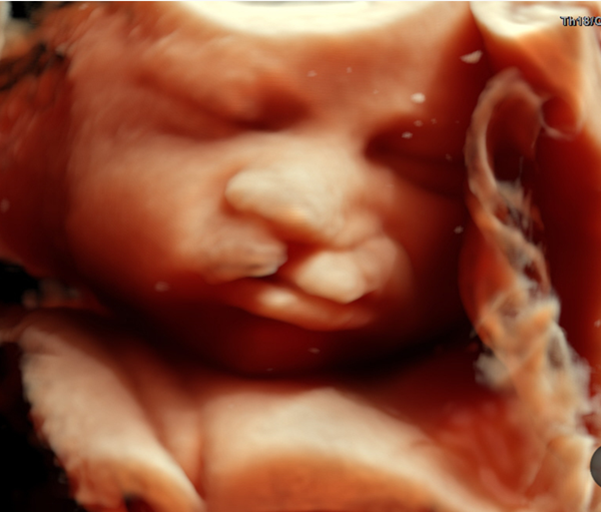

产科_胎儿面部_胎儿颜面三维成像:正常

产科_胎儿面部_胎儿颜面三维成像:唇裂